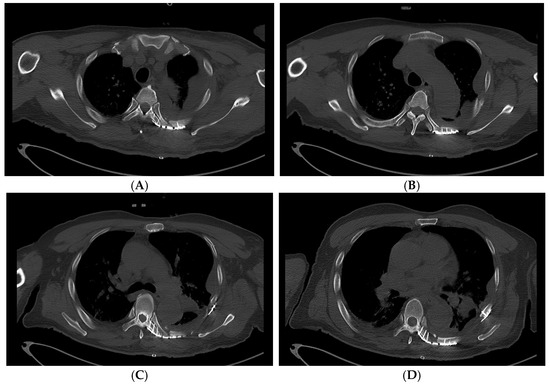

A 64-year-old truck driver fell from the top of a dump truck, estimated to be approximately 3 m high. When the emergency medical service arrived at the scene of the accident, the patient was lying flat on the ground, complaining of chest pain and dyspnea. The initial vital signs were as follows: blood pressure of 100/60 mmHg, pulse rate of 98 beats/min, respiratory rate of 25 breaths/min, and oxygen saturation of 88%. Oxygen was supplied at a rate of 15 L/min with a partial rebreather facial mask, which improved the oxygen saturation to 96%. The patient was transferred to the nearest trauma center. The vital signs measured on arrival at the trauma center were as follows: blood pressure of 125/97 mmHg; pulse rate of 95 beats/min; respiratory rate of 32 breaths/min; and oxygen saturation of 92%. Initial laboratory results showed a hemoglobin level of 12.3 g/dL, a white blood cell count of 11350 per μL, and a lactate level of 2.4 mmol/L, indicative of mild impairment of oxygen delivery. Whole-body computed tomography (WBCT) scan was performed, revealing initial diagnoses, including minor traumatic brain injury with skull fractures and scalp laceration, left clavicle fracture, multiple left-sided rib fractures with ipsilateral hemopneumothorax and pulmonary contusion, and left kidney injury. Rib fractures were observed at the 2nd to the 12th ribs, with moderate to severe displacements. Notably, the displaced 5th and 6th left ribs were positioned such that they nearly damaged the descending thoracic aorta (Figure 1).

Figure 1. Axial views of the initial chest CT scans showing the most displaced left-sided fractured ribs (arrow). The CT images are shown in sequential order from the 4th rib to the 7th rib (AD). (C) The tip of the fractured 6th rib poses an imminent threat to the aorta.